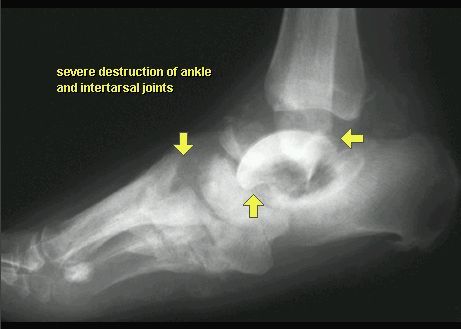

STAW CHARCOTA

RTG